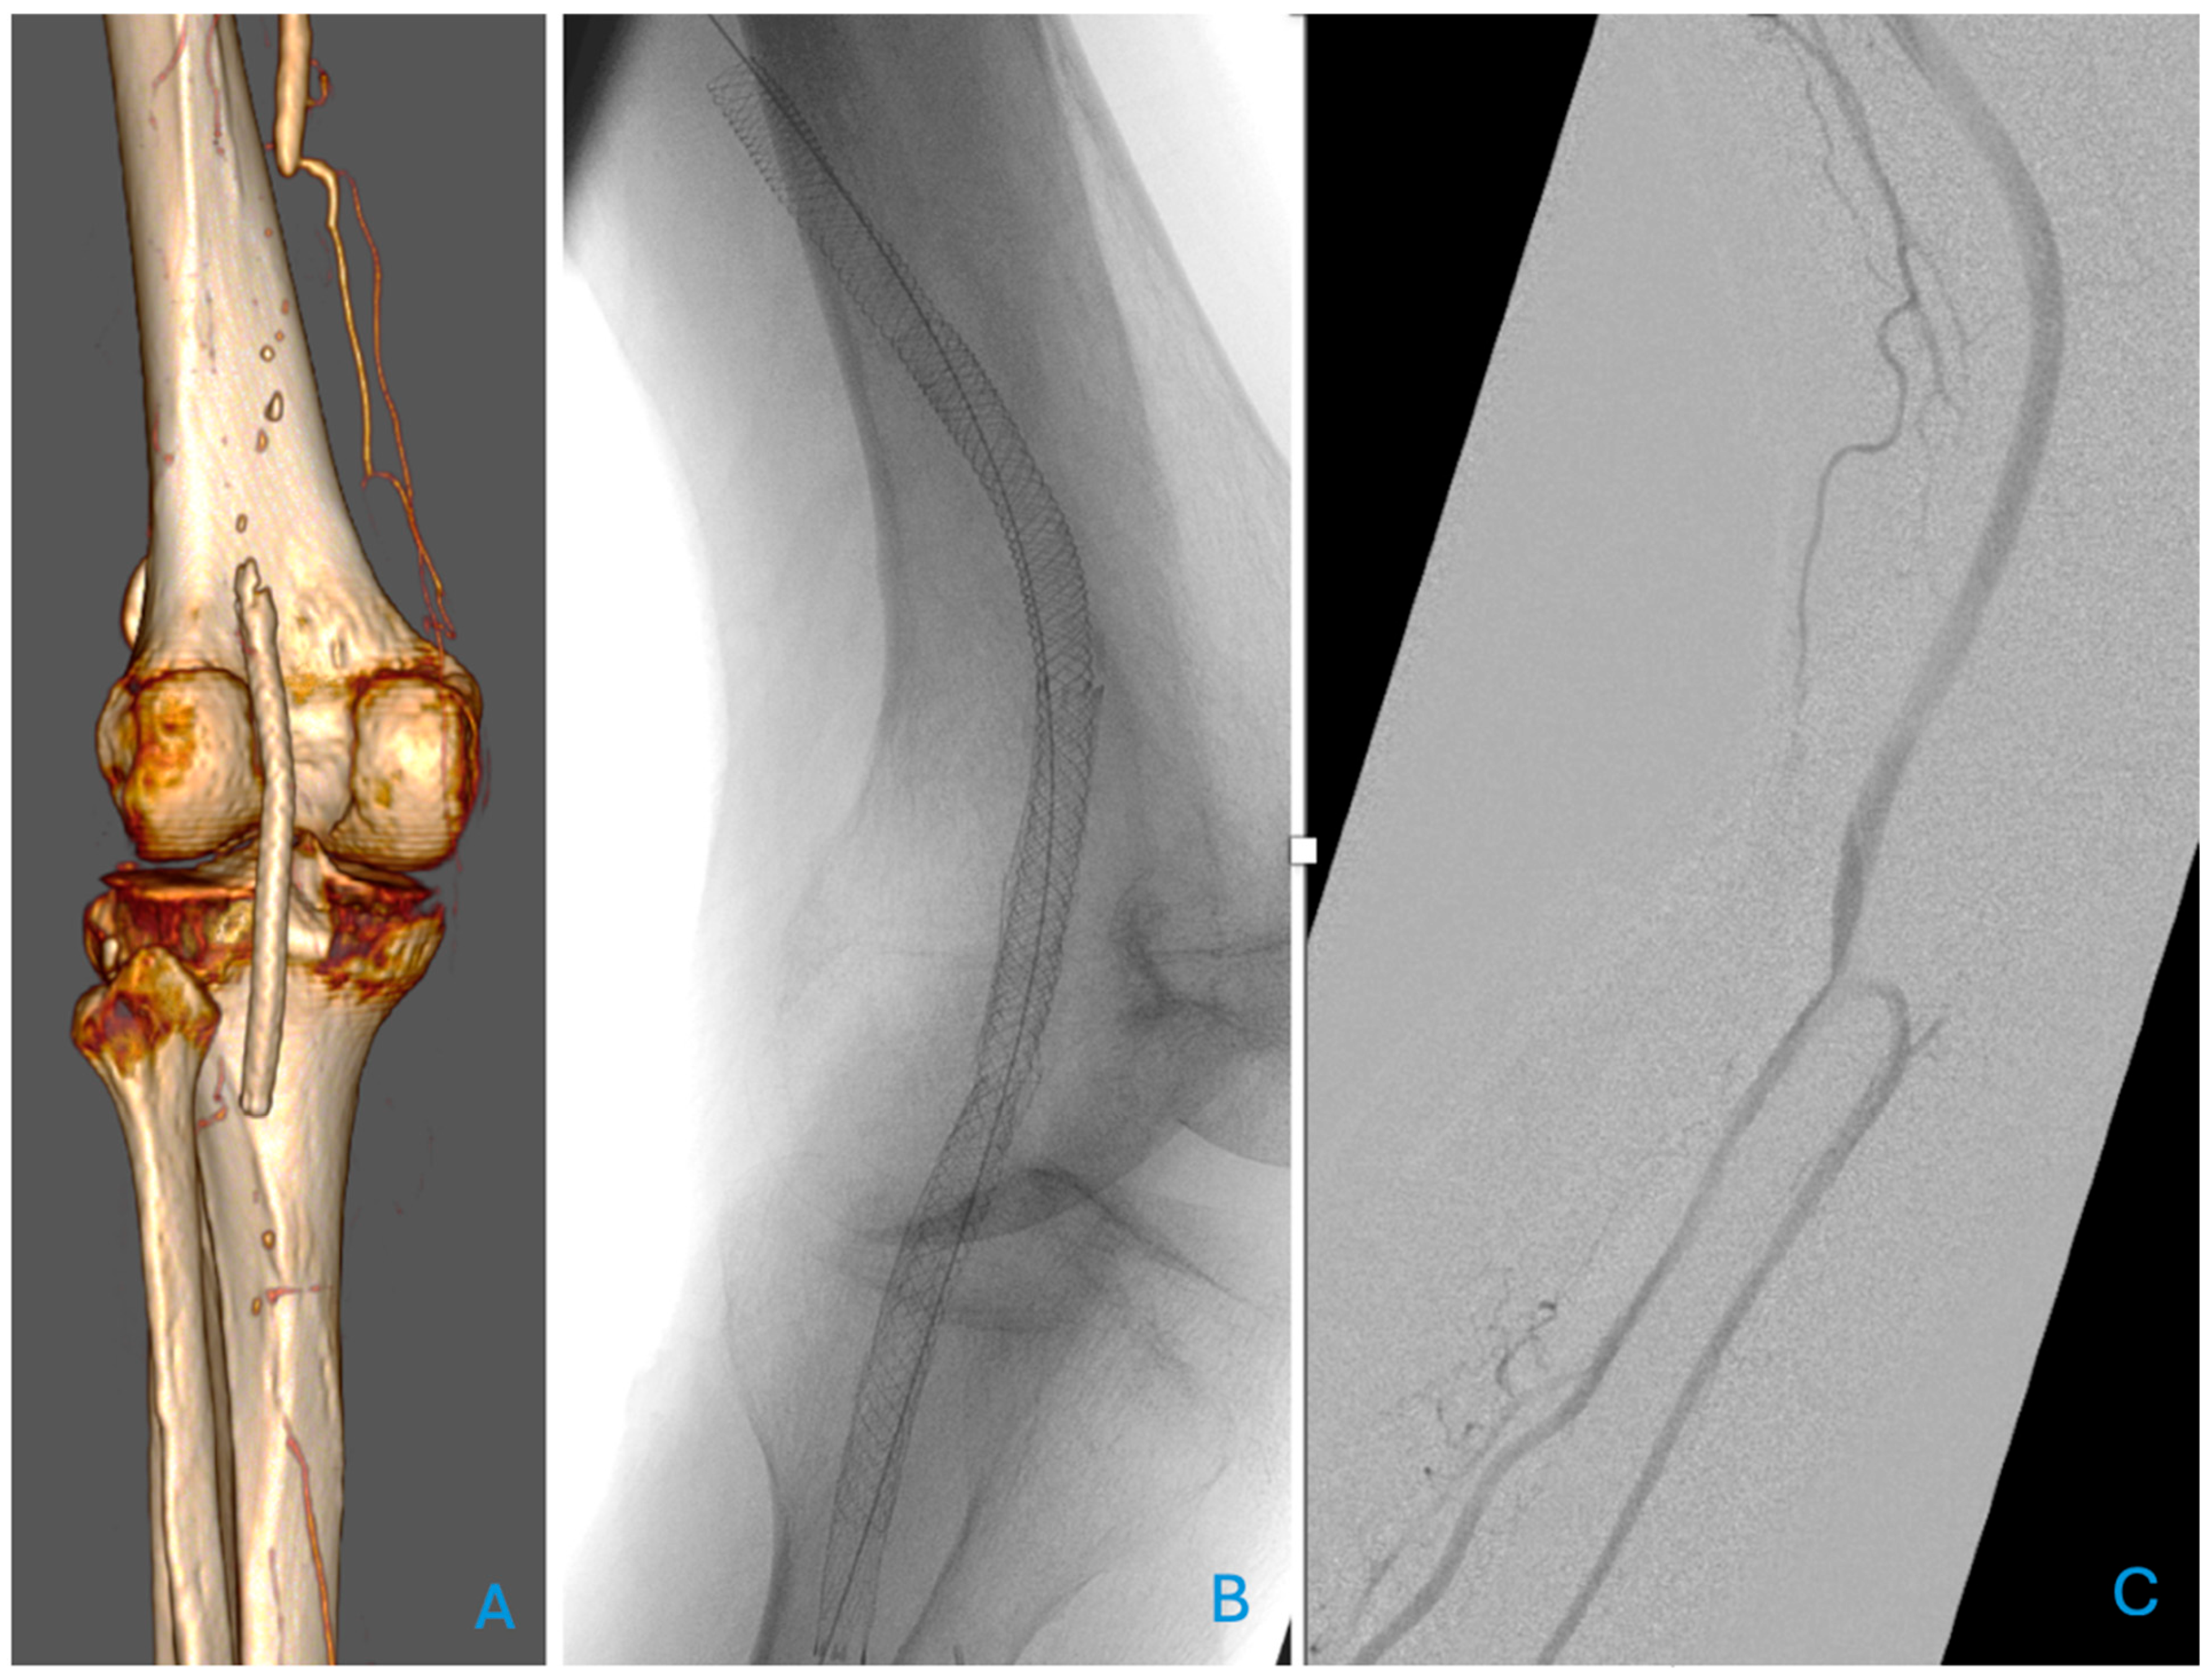

The focus is on self-expanding stents which are particularly suited for the PA due to their high resistance, which is ideal for a segment in movement that will regularly be exposed to compression, i.e., when sitting. Vasculomimetic self-expanding stents are more advanced, with increased flexibility, low force exerted on the treated vessel, and improved fracture resistance. Examples are the Supera Stent (Abbott Vascular, Santa Clara, CA, USA) and the BioMimics 3D (Veryan Medical Ltd., Horsham, UK). The Supera stent is made from interwoven flexible nitinol wires, while the BioMimics 3D stent features a 3D helical geometric design. Vasculomimetic stents have been designed to reduce intimal hyperplasia. This is achieved by promoting a swirling flow, which increases wall shear stress and stabilises the anatomical challenges of this segment [11,23,42]. An example of a patient treated with a vasculomimetic stent is presented in Figure 1, where a relining of a fractured, unsuitable stent for the popliteal artery was necessary.

Figure 1. Relining of an occluded and fractured stent (not dedicated to the popliteal artery) (A) with a biomimetic self-expanding Supera stent (Abbott Vascular, Santa Clara, CA, USA) (B). The completion angiography with knee bending (C) is satisfactory.